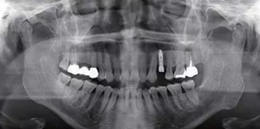

種植完成后可以通過拍攝曲面體層或是根尖片來確認種植體的植入情況,并作為資料加以保存。

圖7 曲面體層片